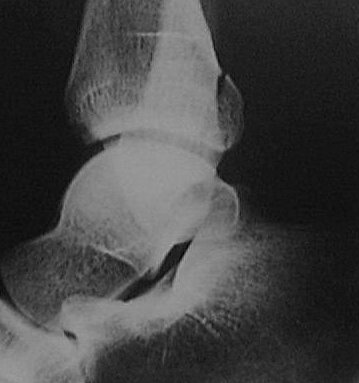

Return to Maisonneuve Fracture